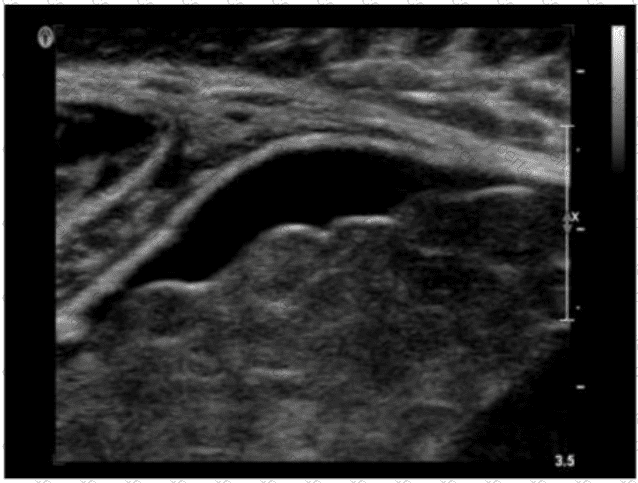

QUESTION DESCRIPTION:

Which patient maneuver would best aid in identifying the pathology demonstrated in this image?

Correct Answer & Rationale:

Answer: D

Explanation:

The ultrasound image demonstrates a classic example of ascites, shown by the anechoic (dark) fluid located between bowel loops or surrounding abdominal organs. In this case, there appears to be a small fluid collection in the peritoneal cavity.

One of the key maneuvers used to differentiate free fluid (such as ascites) from loculated fluid or other structures is to reposition the patient. Asking the patient to “turn from side to side” (Option D) can help in assessing whether the fluid shifts position — a hallmark feature of free intraperitoneal fluid. This positional change is highly useful in confirming the diagnosis and distinguishing ascites from other potential mimics (e.g., cystic masses, lymphoceles, or bowel wall thickening).

In contrast:

Drinking water (A) is often used in imaging the urinary bladder or gastrointestinal tract but not for fluid characterization.

Standing upright (B) may shift fluid but is less practical during real-time ultrasound.

Breathing quietly (C) doesn’t significantly aid in visualizing peritoneal fluid mobility.